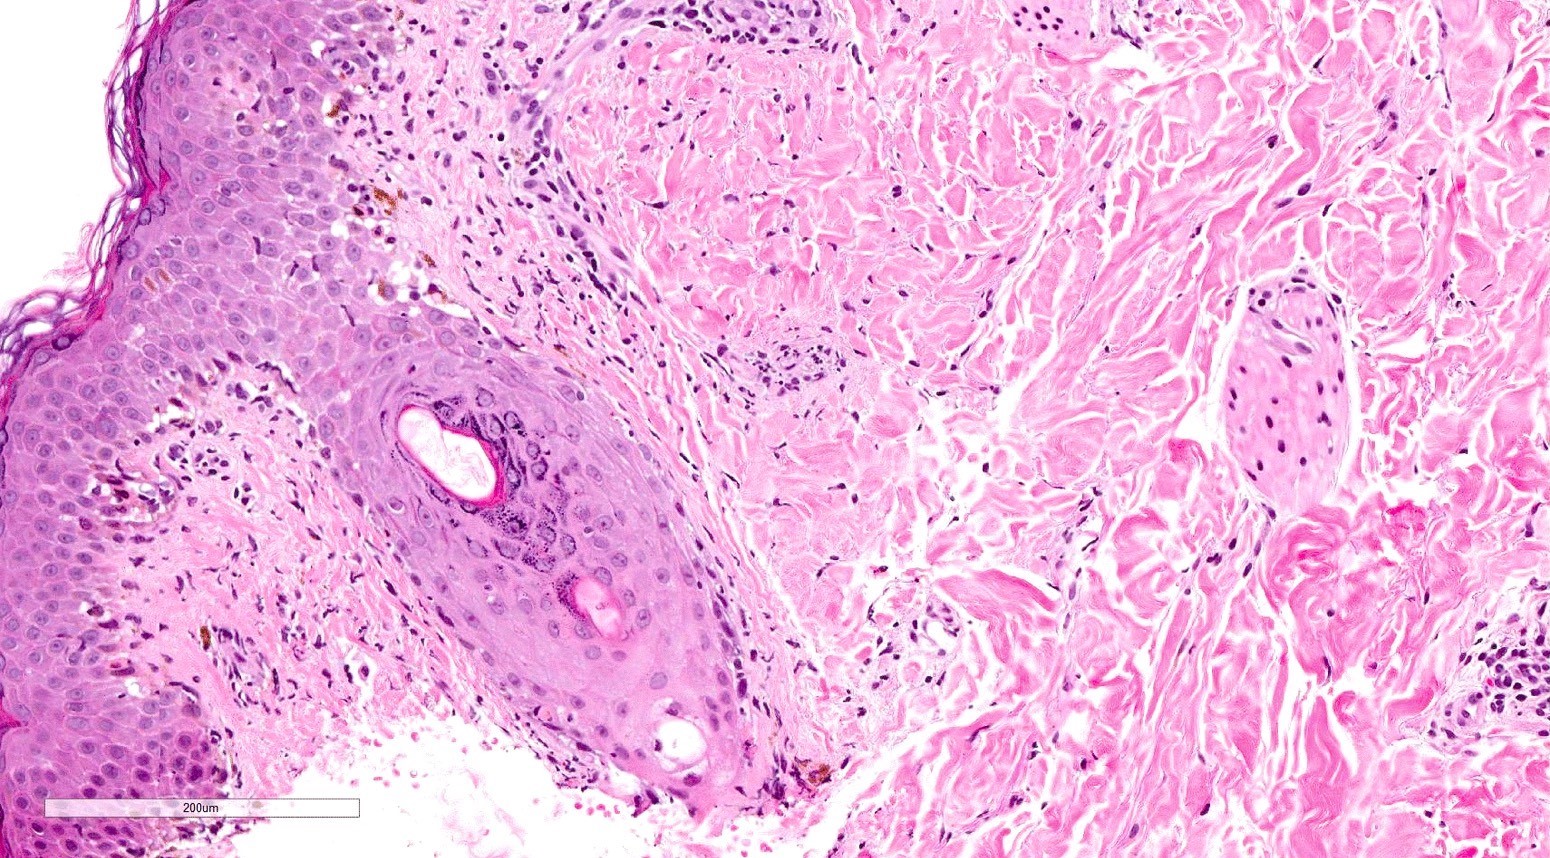

- Chronic GVHD (Biol Blood Marrow Transplant 2015;21:589, Patterson: Weedon's Skin Pathology, 4th Edition, 2015)

- Chronic lichenoid GVHD

- Acanthosis, orthohyperkeratosis, parakeratosis with hypergranulosis

- Underlying band-like lymphocytic infiltrate with basal layer vacuolization and apoptotic keratinocytes

- Periadnexal inflammation can be present

- May be difficult to distinguish from lichen planus without clinicopathologic correlation; satellite cell necrosis is the most helpful clue in GVHD biopsies to distinguish it from lichen planus

- Chronic sclerodermoid GVHD

- Dermal sclerosis (thickened compact collagen with loss of periadnexal fat)

- Manifests with localized morphea-like features, diffuse sclerosis or lichen sclerosus-like features

- Localized morphea-like features and diffuse sclerosis are largely confined to the reticular dermis or subcutaneous septa with little or no epidermal involvement

- Lichen sclerosus-like GVHD: collagen alteration is confined to the papillary dermis (hyalinzation of the papillary dermis), often with residual interface changes characterized by the presence of mild vacuolar alteration, melanophages and sparse superficial perivascular lymphocytic infiltrate

- Chronic lichenoid GVHD

Microscopic (histologic) images

Contributed by Silvija P. Gottesman, M.D. and Ohoud Aljarbou, M.D.